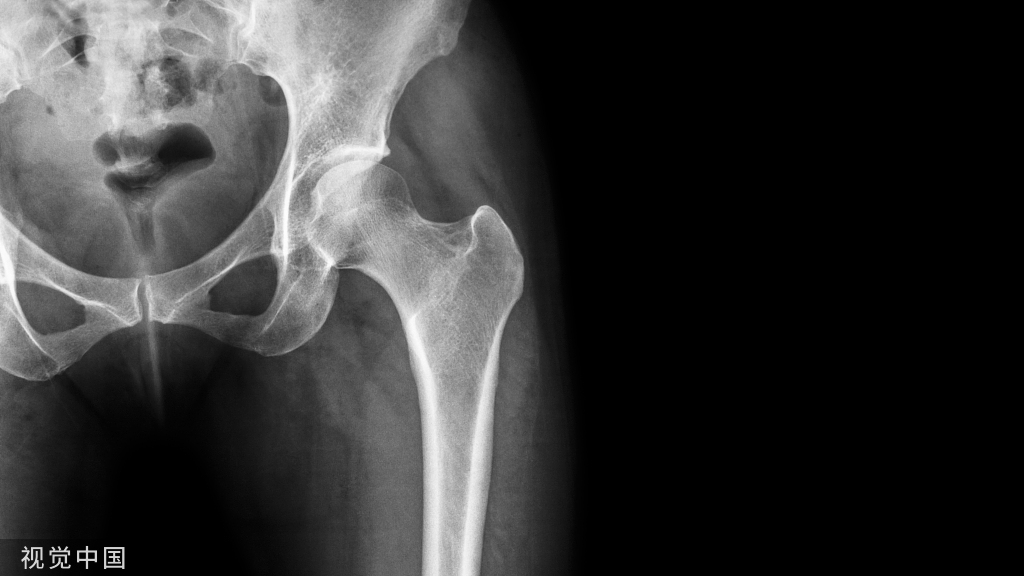

香港大学(港大)医学院于2022年5月19日公布了一项研究,提示感染新冠病毒可能诱发破骨细胞的炎症,致使患者在感染期和康复后期,出现严重的骨质流失。研究团队认为,这可能是一种被忽视的新冠并发症。

为了研究新冠病毒对骨组织代谢的影响,研究团队在叙利亚仓鼠模型鼻内注入新冠病毒,并收集它们受感染后的骨组织样本。通过三维微米级计算机断层成像技术,团队发现感染新冠病毒会引起长骨及椎骨等部位内的小梁骨结构,出现20%~50%不等的严重骨质流失。急性感染所引起的骨质流失,更会持续较长时间。

研究进一步发现,骨质流失与因感染新冠病毒诱导的细胞因子失调有密切关系。这种病理上的骨质缺乏与破骨细胞(一种负责骨组织吸收的细胞)的炎性息息相关,由感染新冠病毒引起的细胞因子失调不单影响破骨细胞分化,而且还在骨骼组织中引起促炎症反应,增强其促进破骨细胞生长的影响。该研究已经由香港大学医学院发表在国际期刊《自然通讯》上。